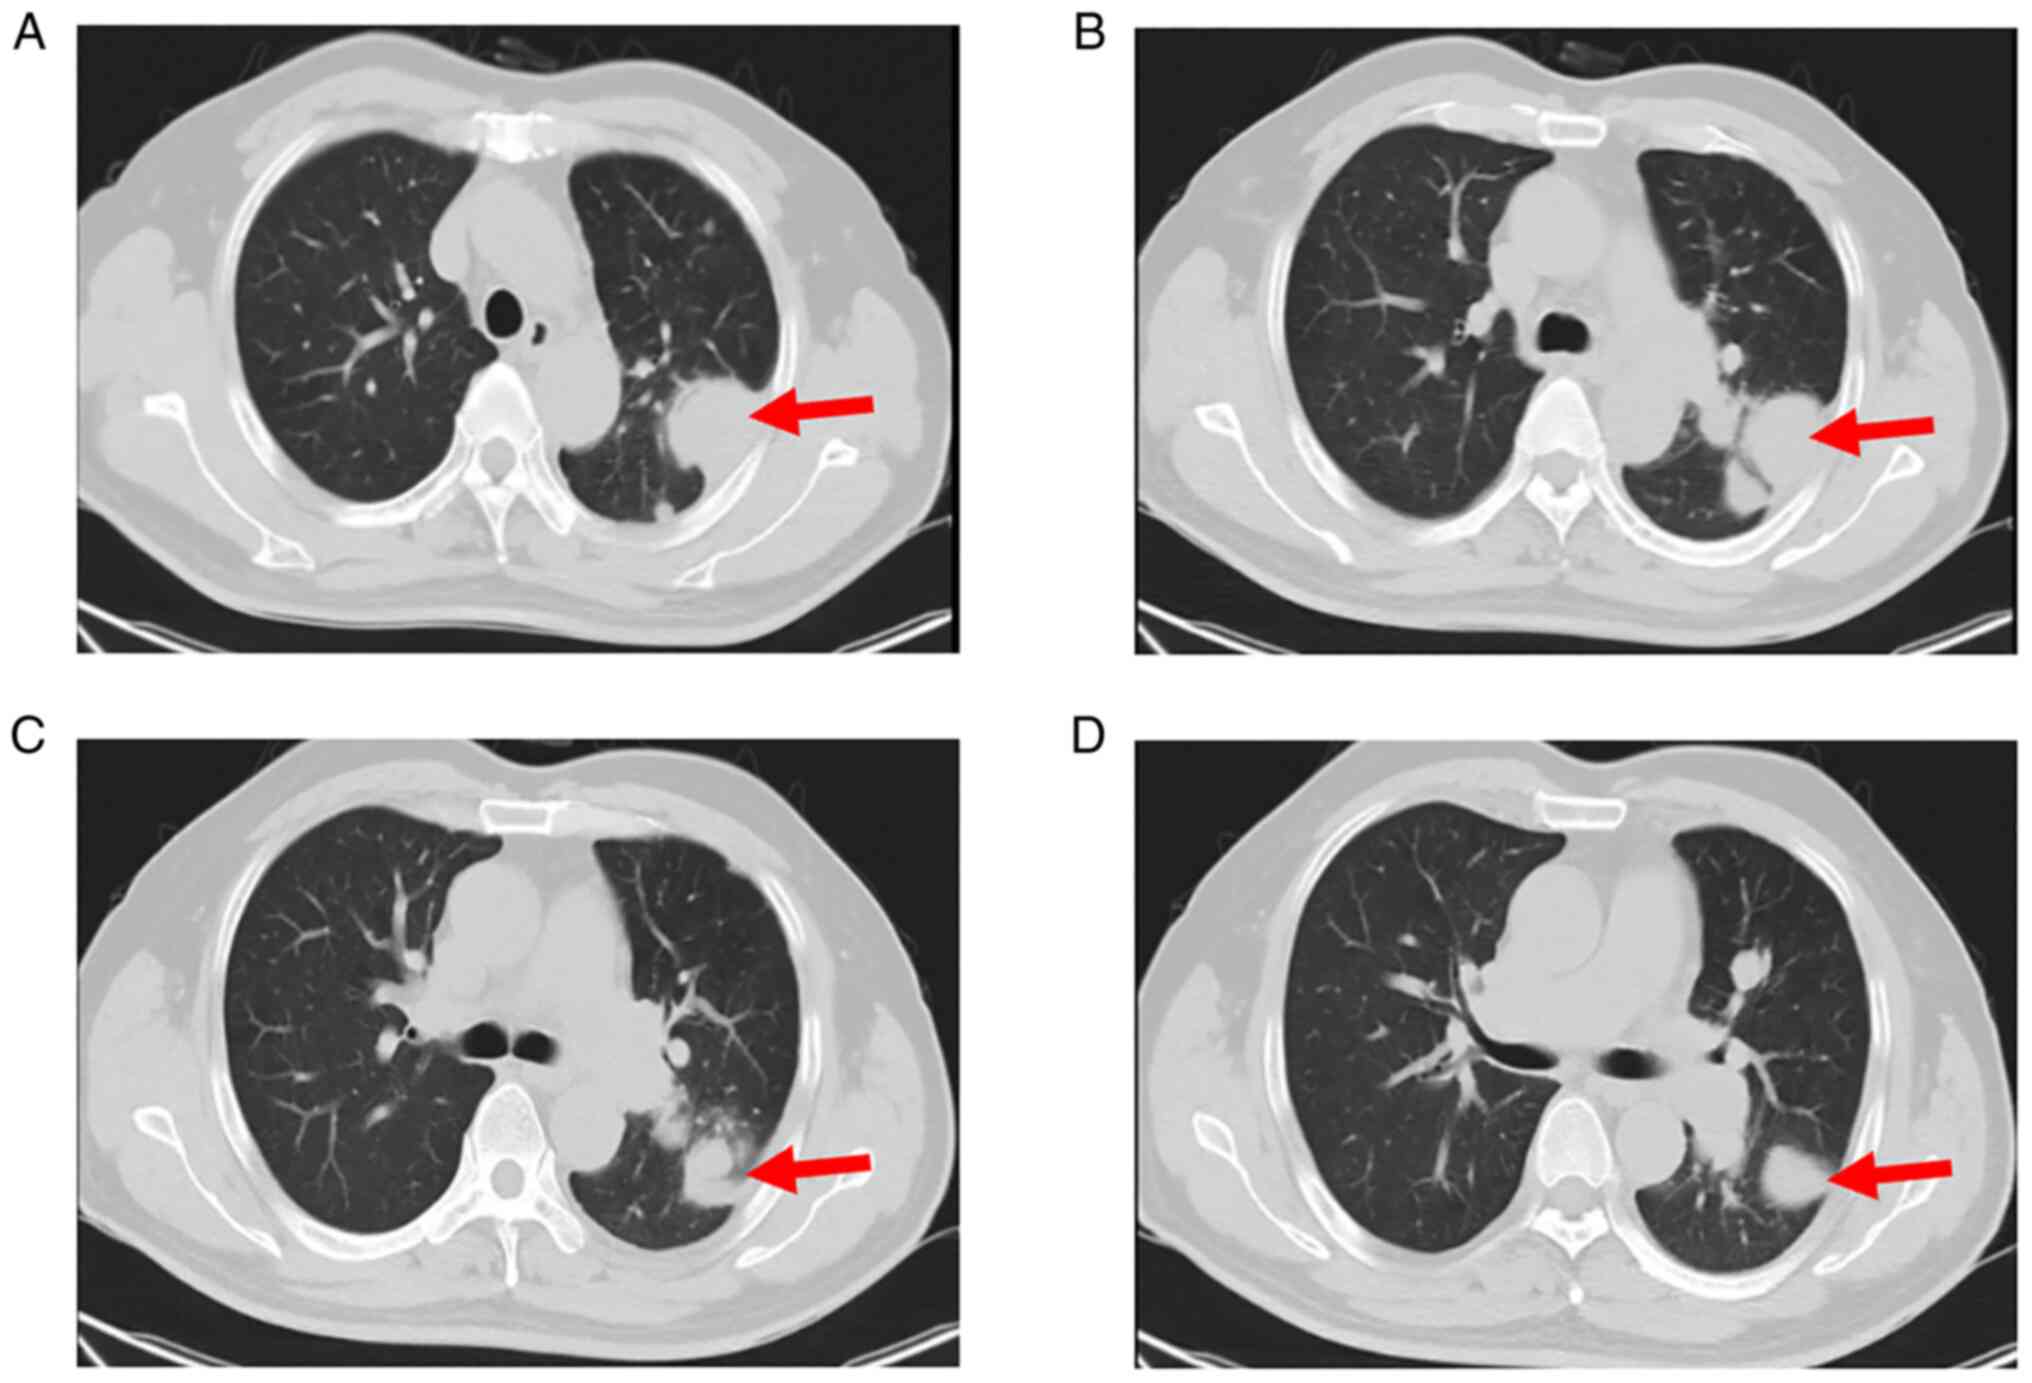

The patient then consulted our department at the First Affiliated Hospital of Fujian Medical University (Fuzhou, China) in May 2021 and received standard anticoagulant therapy for an additional 3 months. The patient's symptoms improved slightly. However, chest CT re-examination (Fig. 2) indicated multiple pulmonary nodules and consequently, the patient was hospitalized. Examination of the patient's family history indicated a lack of evidence supporting any special history or family history. The physical examination indicated pulmonary valve second heart sound > aortic valve second heart sound and no swelling on both of the lower limbs.

Figure 2.

Chest CT re-examination after 6 months of anticoagulation. Multiple solid nodules of different sizes. Lesions with diameters of (A) ~2.81 cm, (B) ~2.47 cm, (C) ~2.24 cm and (D) ~1.73 cm were noted in the left hilum and left lung (red arrow); a certain number of these nodules adhered to the pleura. The larger nodule had the following dimensions: 4.2×3.3 cm.